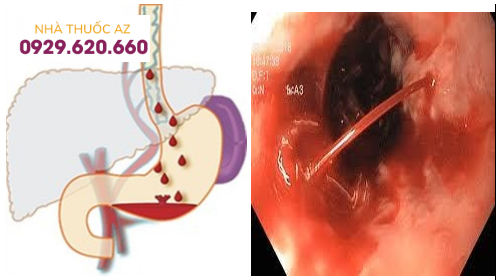

Xuất huyết tiêu hóa do vỡ dãn tĩnh mạch thực quản – hậu quả của giãn tĩnh mạch thực quản không được điều trị

Một trong những biến chứng nghiêm trọng của giãn tĩnh mạch thực quản là xuất huyết tiêu hóa. Biến chứng này có thể gây sốc và dẫn đến tử vong khi người bệnh mất quá nhiều máu mà không được phát hiện và xử trí kịp thời.

Trường hợp xuất huyết tiêu hóa do biến chứng vỡ giãn tĩnh mạch thực quản cần sử dụng thuốc co mạch để làm chậm lưu lượng máu chảy vào tĩnh mạch cửa

Khi giãn tĩnh mạch thực quản bị vỡ và gây chảy máu, tình trạng này cần được kiểm soát và ngăn chặn sớm để hạn chế nguy cơ sốc và tử vong đối với bệnh nhân.